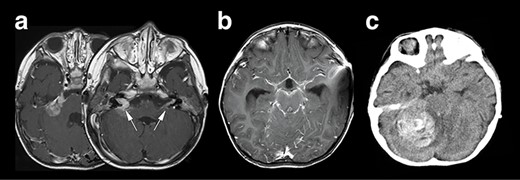

Right hemifacial paresis was the chief complaint of this 2-year-old boy. Initial magnetic resonance imaging (MRI) revealed a solitary lesion in the right cerebellopontine (CP) angle extending into the internal auditory canal (Fig. 1a). A contrast-enhanced T1-weighted image (T1WI) revealed another lesion at the contralateral left facial and vestibulocochlear cranial nerve (Fig. 2a arrows). This case was initially considered as NF2 based on bilateral auditory canal invasion of the tumor. His general condition worsened within 2 weeks, with the tumor hemorrhagically expanding and accompanying communicating hydrocephalus. The patient underwent an emergency ventriculoperitoneal shunt placement, which alleviated his condition. Subsequent neuroimaging revealed that widespread leptomeningeal enhancement surrounded the brainstem and the spinal cord and occupied the subdural and subarachnoid space (Fig. 1b). He developed a sudden severe conscious disturbance 4 weeks after the initial onset of the disease with massive intra-tumoral hemorrhage compressing the brainstem (Fig. 1c). An emergency tumor resection was conducted, achieving subtotal removal of the lesion. The patient’s general condition generally deteriorated, and he died 3 months after the operation, although chemotherapy (ifosfamide, cisplatin, etoposide) was prescribed. The overall survival of the patient was 3.5 months.

Neuroradiological representation of the lesions, T1WI showed a homogeneously enhanced lesion at the cerebellopontine angle spreading to the bilateral auditory canal (white arrows) (a), and a widespread leptomeningeal enhancement was encasing the brainstem (b). Unfortunately, the patient’s condition suddenly deteriorated, and the CT image revealed a massive intra-tumoral hemorrhage compressing the brainstem (c).